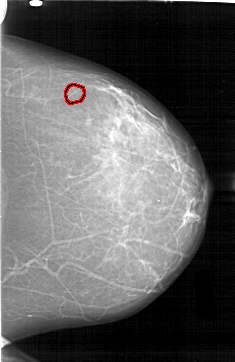

D_4195_1.LEFT_CC

LEFT_CC LINES 6511 PIXELS_PER_LINE 4216 BITS_PER_PIXEL 12 RESOLUTION 43.5 OVERLAY

FILE: D_4195_1.LEFT_CC.OVERLAY

TOTAL_ABNORMALITIES 1

ABNORMALITY 1

LESION_TYPE CALCIFICATION TYPE AMORPHOUS DISTRIBUTION CLUSTERED

ASSESSMENT 0

SUBTLETY 3

PATHOLOGY BENIGN

TOTAL_OUTLINES 1